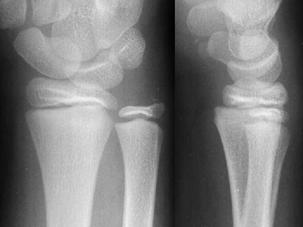

Fractura multisegmentara intertrohanteriana Fractura Salter - Harris I

Fractura Salter - Harris I Fractura Salter - Harris II

Fractura Salter - Harris III

Fractura Salter - Harris IV Fractura Salter - Harris V